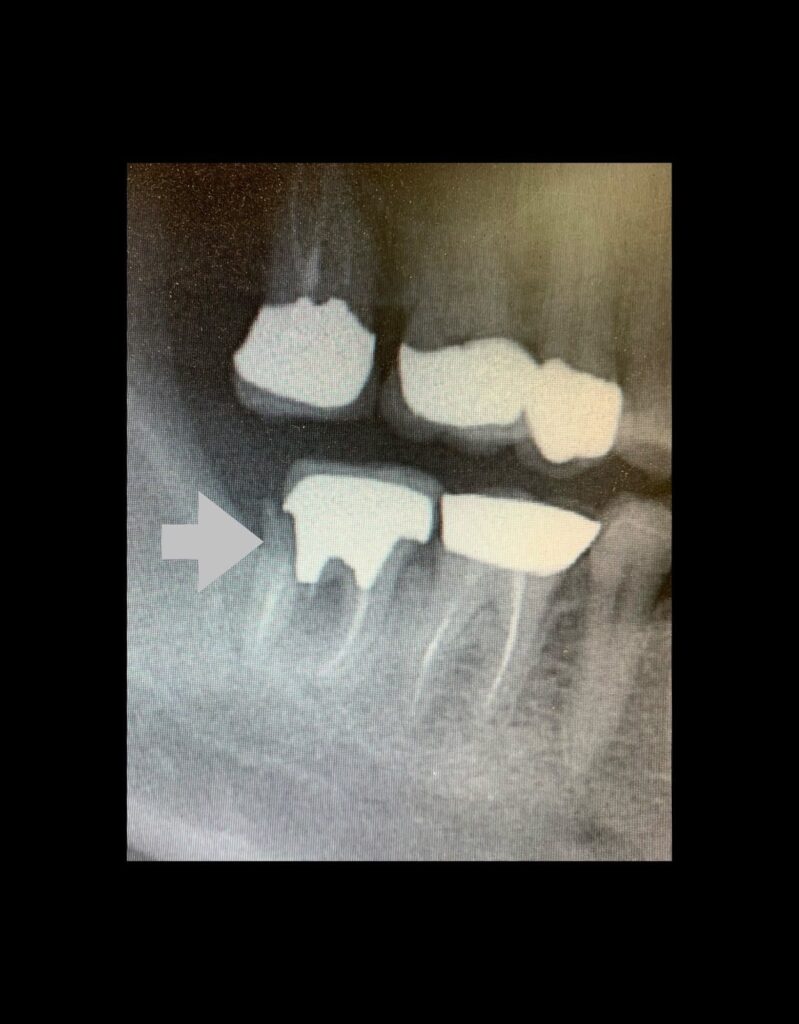

奥歯の噛み締めが強く、歯の根が割れたケース。根っこが割れると多くの場合抜歯になります。